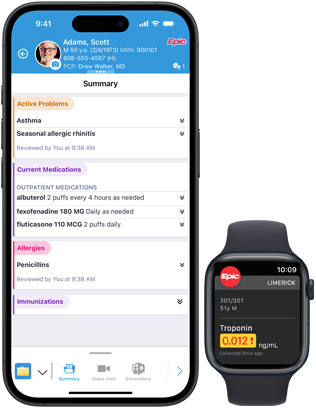

Epic Hyperspace 可協助醫護人員快捷又輕鬆地存取和更新病人記錄。透過使用 AI 技術驅動的臨床摘要、善用 AI 起稿的回應來回答病人訊息,以及診療環境文件記錄,為下一步做足準備。

iPhone 和 Apple Watch 上的 Epic Haiku & Limerick 讓獲授權的臨床醫生可在 iPhone 上安全地存取病人記錄。使用 Epic Limerick,實時更新及通知可在 Apple Watch 及 iPhone 上顯示。